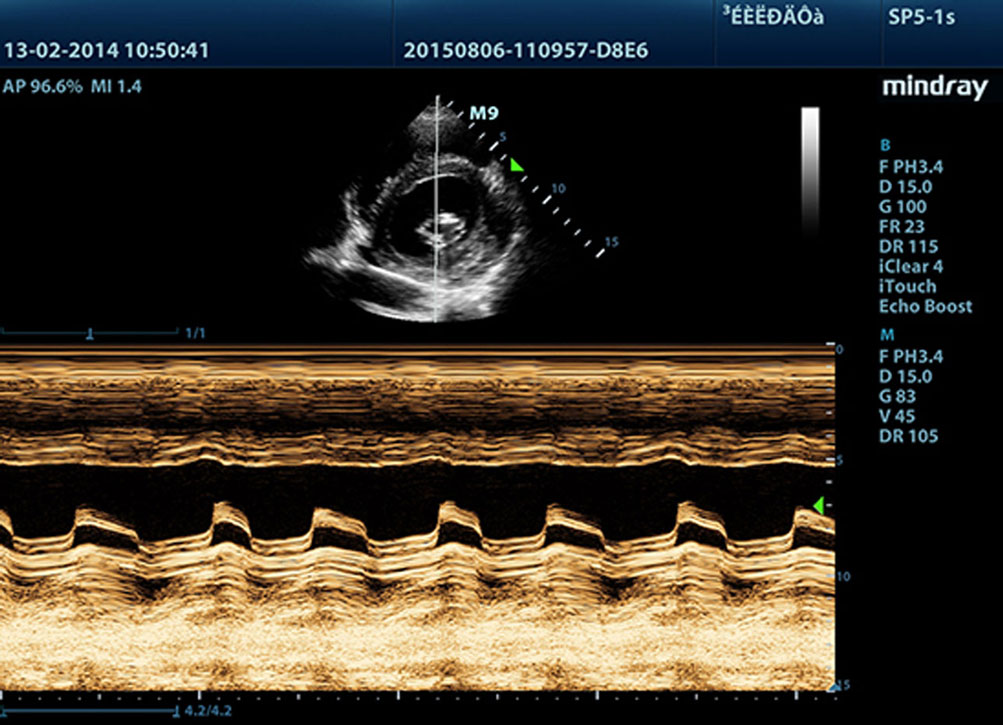

Funkcja anatomicznego trybu M?

Funkcja ta daje mo?liwo?? precyzyjnej obserwacji cz??ci anatomicznej poprzez swobodne umieszczanie linii trybu M pod dowolnym k?tem. Mo?na uzyska? lepsze obrazy dzi?ki jednoczesnemu wy?wietlaniu maksymalnie trzech linii trybu M.

Funkcja anatomicznego trybu M z dopplerem tkankowym

S?u?y do dok?adnej oceny ruchu mi??nia sercowego w rÃģ?nych fazach, przy jednoczesnym okre?laniu synchronizacji mi??nia sercowego. Wysoka cz?stotliwo?? od?wie?ania zapewni PaÅstwu dok?adne wyniki.